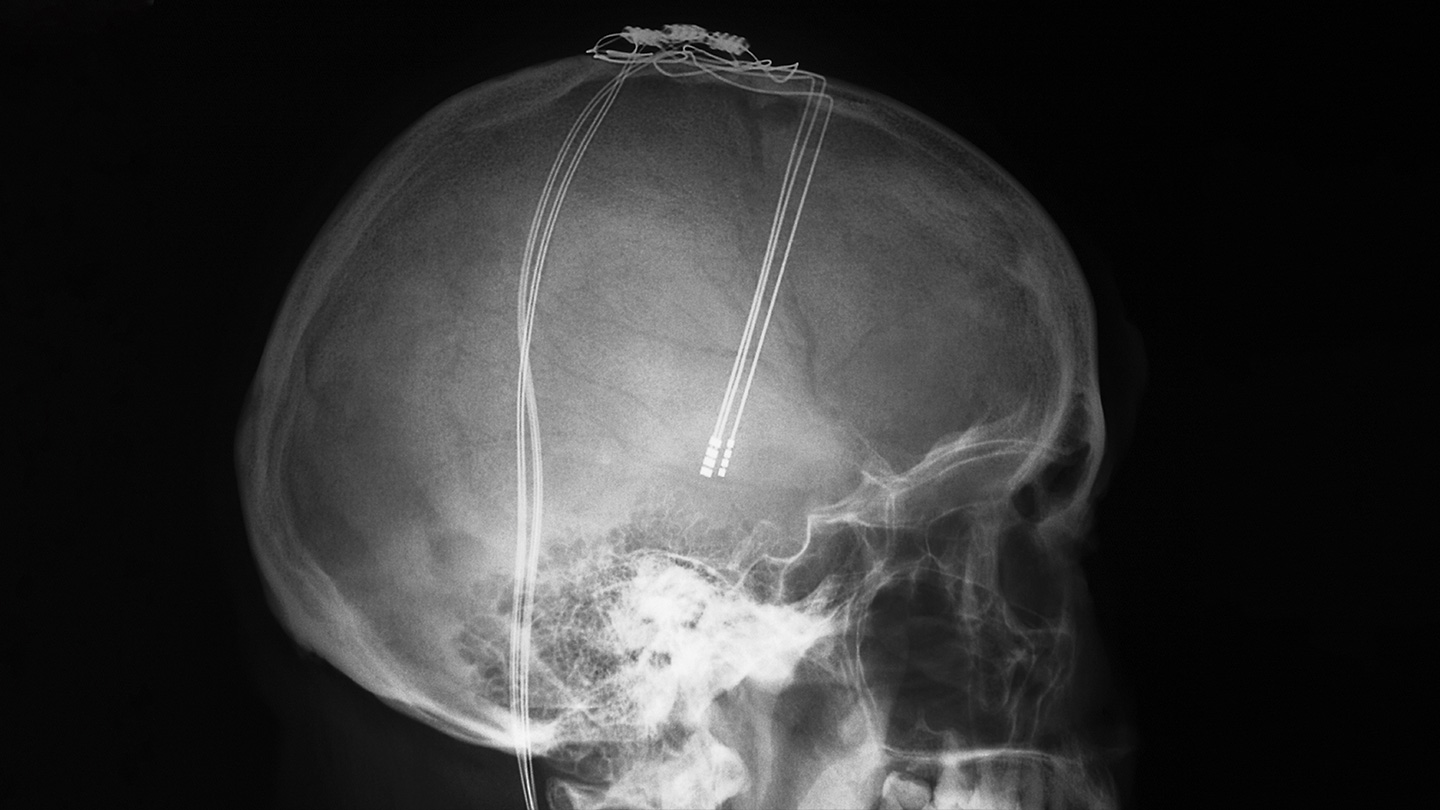

Already, a technique known as deep brain stimulation, or DBS, uses electrodes surgically implanted in people’s brains to tweak the behavior of brain cells. Such electrode implants are helping reduce Parkinson’s tremors, epileptic seizures and uncontrollable movements caused by Tourette’s syndrome. Mood disorders like Sarah’s have been targeted too.

The central idea of DBS — that the brain can be fixed by stimulating it — is not new. In the 1930s, psychiatrists discovered that a massive wallop of seizure-inducing electricity could sometimes relieve psychiatric symptoms. In the 1940s and 1950s, researchers studied whether more constrained electrical stimulation could help with disorders such as depression.

In 1948, for instance, neurosurgeon J. Lawrence Pool of Columbia University’s Neurological Institute of New York implanted electrodes to stimulate the brain of a woman with severe Parkinson’s who had become depressed and lost weight. Soon, she began to “eat well, put on weight and react in a more cheerful manner,” Pool reported in 1954.

The experiment ended three years later when one of the wires broke. “It is the writer’s conviction that focal controlled stimulation of the human brain is a new technique in psychosurgery that is here to stay,” Pool wrote.

Compared with those early days, today’s scientists understand a lot more about how to selectively influence brain activity. But before a treatment such as Sarah’s is possible, two major challenges must be addressed: Doctors need better tools — nimble and powerful systems that are durable enough to work consistently inside the brain for years — and they need to know where in the brain to target the treatment. That location differs among disorders, and even among people.